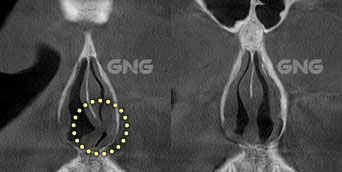

코막힘으로 내원하셨습니다. 코막힘 원인을 파악한 후비밸브 재건술, 비중격 재건술,하비갑개 절제술을함께 진행하신 분입니다. CT 사진을 보면 수술 전후의 변화를극명하게 확인하실 수 있는데요. 수술 전후 사진으로 비교했을 때,비강의 양쪽의 넓이가 비슷해지는 것이가장 이상적인 수술 결과입니다. <코막힘 원인> 수술 전 CT사진에서 뼈 부분이 왼쪽으로 치우쳐있고,왼쪽의 비강이 완전히 막혀있는데요. 위쪽 . . .